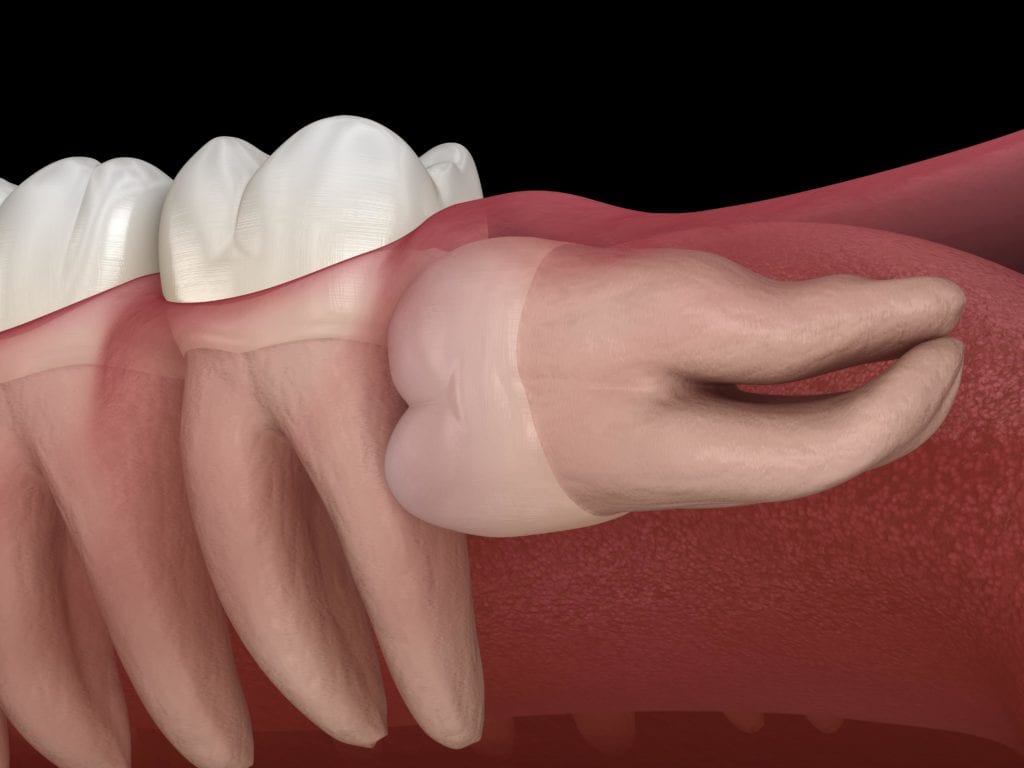

An impacted wisdom tooth may partially emerge so that some of the crown is visible (partially impacted), or it may never break through the gums (fully impacted). Whether partially or fully impacted, the tooth may:

tooth Grow at an angle toward the next tooth (second molar)

tooth Grow at an angle toward the back of the mouth

tooth Grow at a right angle to the other teeth, as if the wisdom tooth is "lying down" within the jawbone

tooth Damage to other teeth: If the wisdom tooth pushes against the second molar, it may damage the second molar or increase the risk of infection in that area. This pressure can also cause problems with crowding of the other teeth or require orthodontic treatment to straighten other teeth.